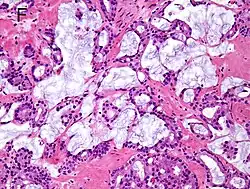

| Mucinous adenocarcinoma | 0.2%[12] |

|

Tumorous glands: | 4+4=8 for irregular cribriform glands floating in mucin.[1] | ||